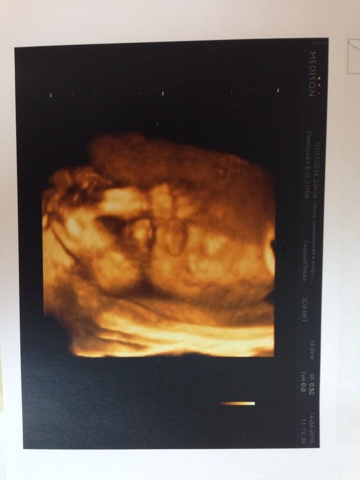

Наши 23 недельки и фото 3д узи

УЗИ, КТГ, доплерСходила недавно к Тё на 3д узи.Все реальнее становится наш малыш.Специально для родственников сделали видеозапись узи, там видно как он сосет пальчик и зевает (ну либо просто открывает рот), это просто что то